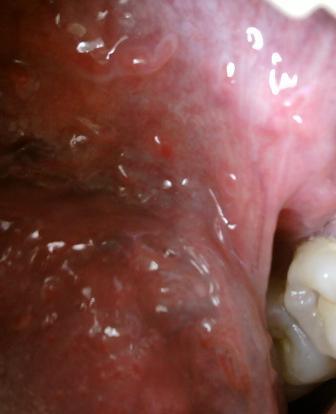

石家庄九州皮肤病医院 > 尖锐湿疣 > > > 尖锐湿疣需要掌握科学的治疗方法尖锐湿疣是性传播疾病中比较严重的,因此专家在这里温馨提示:对于疾病的诊治一定要引起重视,切记不能耽误诊治。

尖锐湿疣需要掌握科学的治疗方法要想早日治愈疾病,就应该及时去正规的专业医院就诊,这是因为任何疾病初期都是治疗疾病的最佳时期。现在医学对于疾病的诊治是很重视的,因此专家在这里温馨提示:及时选择适合的治疗方法,坚持诊治,才能更好的治愈疾病。疾病的治疗是需要时间的,因此希望大家及时诊治,切记不能贻误治疗。